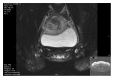

Background. Mullerian duct anomalies (MDAs) are congenital defects of the female genital system that arise from abnormal embryological development of the Mullerian ducts. A didelphys uterus, also known as a "double uterus," is one of the least common amongst MDAs. This report discusses a case of didelphys uterus that successfully conceived, carried her pregnancy to term, and delivered vaginally without any significant complications. Case. Patient is a 29-year-old G2P0010 from Bangladesh, initially came a year prior in her first pregnancy, with spontaneous abortion (SAB). Pelvic Sonogram at that time showed a diagnosis of bicornuate versus didelphys uterus. There were no renal anomalies on subsequent abdominal CT scan. Patient presented with the second pregnancy and had uncomplicated prenatal care and did not have signs of preterm labor; fetus showed appropriate growth and the pregnancy was carried in the left uterus. Patient presented at 38 4/7 wks with Premature Rupture of Membrane and underwent induction of labor with Cytotec. Antibiotics were started for chorioamnionitis. Patient had a vaginal delivery with left mediolateral episiotomy and complete tear of vaginal septum. Third stage of labor was complicated with retained placenta, which was removed manually in the operating room with total EBL of 600 cc.